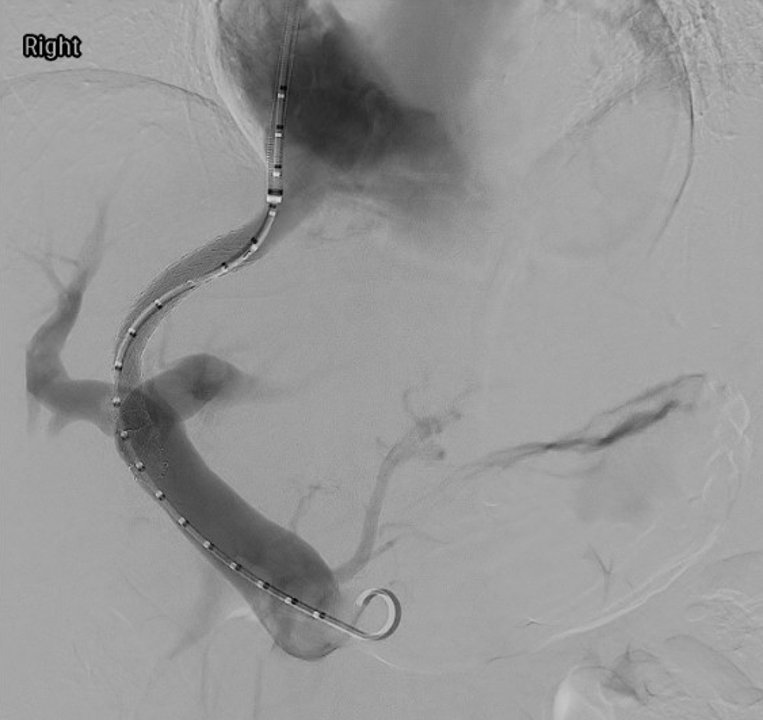

Our research utilizes advanced flow imaging and computational fluid dynamics modeling to map complex blood flow patterns in healthy, diseased, and stented veins. We aim to uncover how chronic venous disease and interventions like stent placement alter hemodynamics, providing critical insights to optimize treatments for conditions like iliac vein compression (May-Thurner) syndrome and post-thrombotic sequelae.

- Reference: Li, N., Ferracane, J., Andeen, N., Lewis, S., Woltjer, R., Rugonyi, S., Jahangiri, Y., Uchida, B., Farsad, K., Kaufman, J.A. and Al-Hakim, R., 2022. Impact of Postthrombotic Vein Wall Biomechanics on Luminal Flow during Venous Angioplasty and Stent Placement: Computational Modeling Results. Journal of vascular and interventional radiology: JVIR, 33(3), pp.262-267. https://doi.org/10.1016/j.jvir.2021.12.006